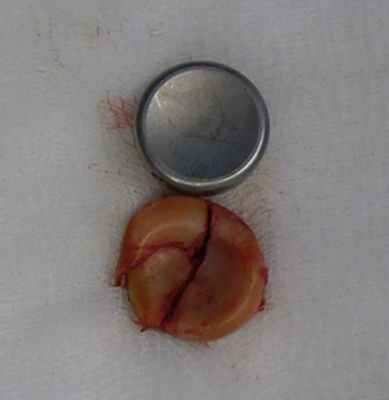

Во время операции выявлен многооскольчатый перелом головки лучевой кости (рис. 3, рис. 4).

![]() | ![]() |